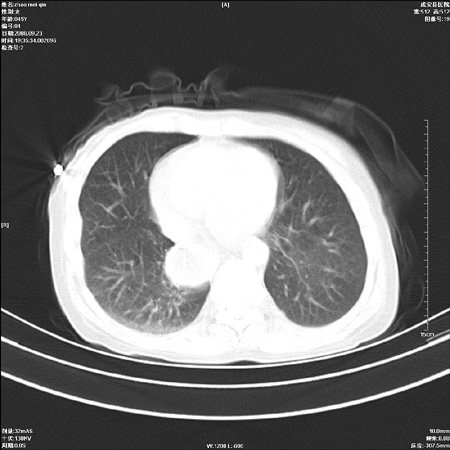

标题: CT15861:女 60 外伤后1小时 胸疼 [打印本页]

标题: CT15861:女 60 外伤后1小时 胸疼

外伤后1小时 胸疼 是外伤后引起的吗?

食道ca术后胸腔胃,右肺挫伤?

非外伤性改变,典型的贲门失迟缓症

食道扩张明显下端逐渐变窄,大量食物存留,象贲门失迟缓症。